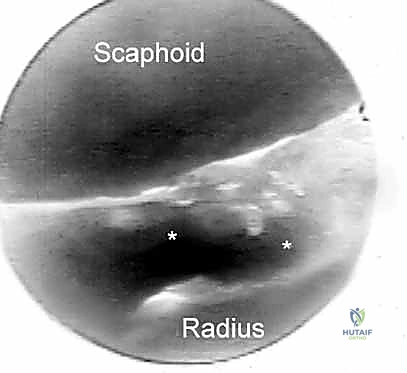

- Function: Indicated for evaluating the dorsal radiocarpal ligament (DRCL) and the palmar portion of the scapholunate interosseous ligament (SLIL). It provides a clear view of dorsal rim fragments for arthroscopic reduction of intra-articular distal radius fractures.